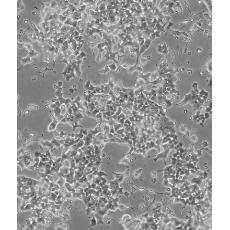

Beta-TC-6

中文名稱 小鼠胰島素瘤胰島β細胞

組織來源 胰島素瘤

細胞種屬 mus musculus, mouse

生長特性 adherent

培養基 DMEM+15% heat-inactivated FBS+1% P/S

形態特征 epithelial

傳代方法 1:2-1:4

細胞描述 這株細胞來源于轉基因小鼠中生長的一個胰腫瘤(胰島素瘤)。這種小鼠攜帶了大鼠胰島素II基因啟動子調控的SV40早期基因的假基因結構。細胞包含豐富的胰島素和小量的胰高血糖素及生長抑素。響應葡萄糖而分泌胰島素